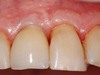

Un brossage excessif sur des gencives de faible épaisseur est souvent la cause des dénudations radiculaires traumatiques.